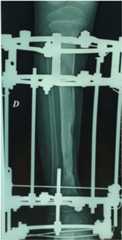

Fig. 1.

X-ray of the right tibia: pathological fracture with extensive bone destruction following acute osteomyelitis.

Bone consolidation underway 3 months after placement of the Ilizarov external fixator and antibiotic therapy.

Fig. 4.

X-ray at 6 months of Ilizarov external fixator.

Fig. 5.